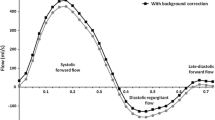

Assessment of PNF

PNF was underestimated relative to ANF by small, but statistically significant, differences (5.4–11.7% of mean flow, p < 0.04) across all three 4DF CMR comparisons and trended towards a significant difference for 2D CMR (9% of mean flow, p = 0.055) (Table 2) (Fig. 2). These mean differences were overall similar between methods (p > 0.35). PNF and ANF correlated stronger by 4DF (PV, MPA, BPA: r = 0.77–0.87, p < 0.001) than 2D CMR (r = 0.68, p < 0.001) (Table 2). Specifically, measurement of PNF at the level of the PV by 4DF CMR demonstrated the strongest correlation with ANF (r = 0.87, p < 0.001) and lowest mean difference (3.5 ± 9.4 mL/beat). Measurements of ANF and PNF at the PV had higher variance by 2D CMR than 4DF CMR; LOA for 2D CMR were − 33 mL/beat (− 41.8% of mean) to 47 mL/beat (59.6% of mean) compared to LOA for 4DF CMR of − 16 mL/beat (− 23% of mean) to 24 mL/beat (34% of mean). Similarly, the absolute mean difference between ANF and PNF evaluated at the PV was significantly larger using 2D CMR than 4DF (p < 0.001).

Bland Altman plots comparing ANF and PNF by 2D CMR (a) and 4DF CMR (b–d, measured at the PV, MPA, and BPA, respectively); differences are calculated as ANF–PNF. e, f directly compare PNF and PR% measured at the PV between 2D and 4DF CMR. Units = mL/beat (a–e) and % regurgitation (f). The mean difference, represented as the solid line, is reported as X (% of mean volume or regurgitation). The limits of agreement are represented with dashed lines. ANF aortic net flow, BPA branch pulmonary arteries, MPA mean pulmonary arteries, PNF pulmonary net flow, PR pulmonary regurgitation, PV pulmonary valve

PNF showed good agreement between 2D and 4DF CMR (mean difference 5.4 ± 19.0 mL/beat, p = 0.11) and correlated moderately (r = 0.67, p < 0.001). Inter-rater reliability of PNF was excellent for 2D (ICC = 0.80) and 4DF CMR (ICC = 0.87) (Table 5). The degree of PR ranged from mild to moderate with good agreement between methods (median (IQR): 2D PC 23.4% (5.4–40.8%); 4DF 25.8% (10.5–36.6%); p = 0.23) and a strong correlation (ρ = 0.78, p < 0.001).